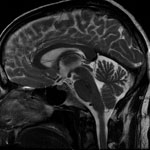

- MRI and MR angiography

MRI (magnetic resonance imaging) is a noninvasive diagnostic test that takes detailed images of the soft tissues of the body. Unlike X-rays or CT, images are created by using a magnetic field, radio waves, and a computer. It allows your doctor to view your spine or brain in slices, as if it were sliced layer-by-layer and a picture taken of each slice. This test can help diagnose tumors, strokes, and disc herniations.